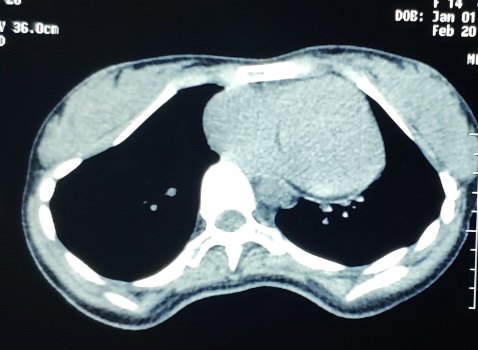

两位Wang手术患儿诊断明确,为漏斗胸,年龄均为2岁。采用标准Wang手术实施操作,手术均在10分钟内完成。鸡胸患者为青年女性,前突主要位于胸骨角附近,采用Wenlin手术实施操作,切口位于腋下,以一条钢板完成矫形。复杂畸形患者为13岁女孩,患者前胸壁正中上半前突,两侧胸壁锁骨中线附近凹陷,CT截面呈近似的“凸”字形改变,合并脊柱前突畸形,生理弯曲消失,无法平卧。手术在全麻下完成,术中采用平卧位,背部与腰部垫高。于两侧胸壁做切口,游离凹陷表面骨性结构,以两条钢板塑形。4台手术操作均顺利,没有出现并发症,术后胸廓外观塑形满意。

今天的复合型畸形患者虽然前胸壁明显前突,但由于同时合并了脊柱的前突畸形,术中不适宜对突起做过度矫正。术中我们采用较长的钢板做塑形,主要的目的是将侧胸壁的凹陷消除,以缓解或者解除术前的症状。

在对此患者实施手术的过程中我们发现,其双侧胸腔均有积液,说明心脏功能明显受损。术前患者有明显的呼吸功能障碍,除了肺部直接受压对呼吸功能的影响外,心脏功能不全也是重要的原因。术中胸壁两侧的凹陷均被消除,术后呼吸功能指标明显改善。